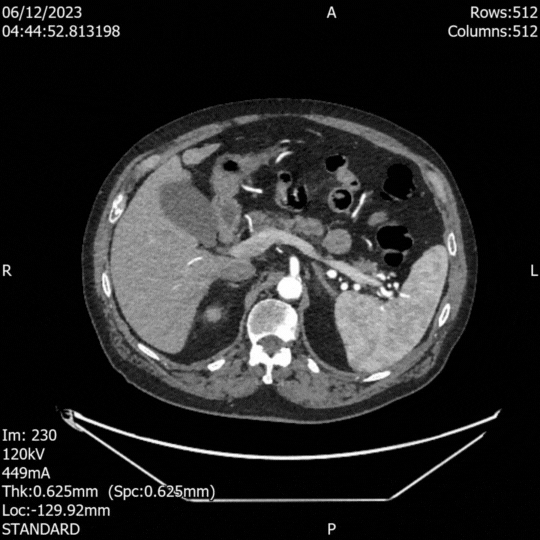

History and physical examination are unreliable in making the diagnosis. Alternative imaging techniques, such as computed tomography (CT), take time to organize and require the transfer of a potentially unstable patient out of the ED.

The sensitivity and specificity of an emergency physician-US Scan for Abdominal Aortic Aneurysm (AAA) is very high, detecting it in at least 97% of cases (sensitivity 97-100%, specificity 94-100%) [4]. Additionally, if an aortic dissection extends to the abdominal aorta, its characteristic appearance of a mobile “flap” might also be seen.

Acute Aortic Syndrome (AAS) comprises a group of serious diseases, including acute aortic dissection, aortic intramural hematoma, and penetrating aortic ulcer. The clinical presentation and features of these processes can be similar or as nonspecific as the ruptured AAA. US can help differentiate between dissection or ruptured aneurysm; however, its sensitivity for aortic dissection is low and not comparable to AAA. Ultrasound is not a reliable tool to rule out aortic dissection, so if suspected, an angio CT study should be arranged. Likewise, US is insensitive in the detection of retroperitoneal blood. If you detect AAA in a shocked patient, assume it has ruptured or is leaking [1]. Furthermore, the differential diagnosis of severe, acute epigastric pain in an unstable patient is broad, and none of these differentials can be accurately diagnosed or ruled out by emergency US.

AORTIC ANEURYSM

In adults, the normal anteroposterior aortic diameter is less than 2 cm, and 3 cm or more is considered dilated. The diameter of the common iliac arteries should not be more than 1.5 cm. Most AAAs occur below the renal arteries. As an aneurysm becomes larger it will dilate faster, leading to a greater risk of rupture. This risk remains low if the diameter is less than 5 cm. By contrast, there is a clear tipping point after surpassing 5.5 cm, as the annual incidence of rupture grows from <1% to 9.4% (5)